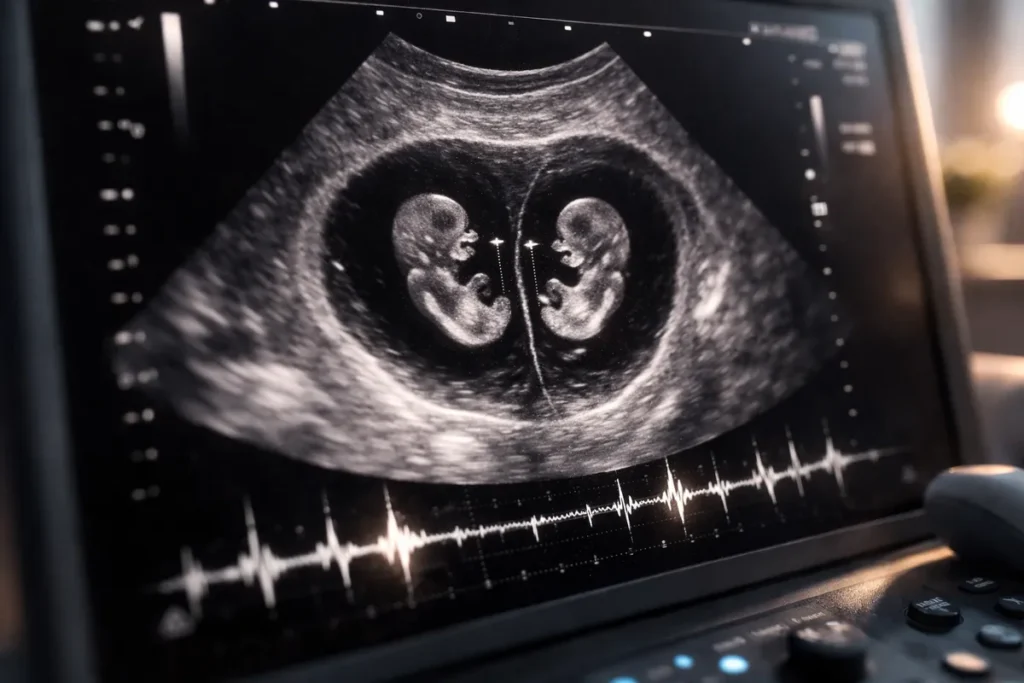

Et parfois aussi… celui où l’on découvre qu’il y en a deux.

Dans notre cas, c’est aussi lors d’une échographie précoce que nous avons appris que nous attendions des jumeaux.

C’est souvent à ce moment que certains couples découvrent qu’ils attendent des jumeaux.

Vrais ou faux jumeaux : ce que révèle la première échographie

Lorsque deux embryons sont visibles, la première échographie permet souvent de déterminer s’il s’agit :

- de vrais jumeaux

- ou de faux jumeaux